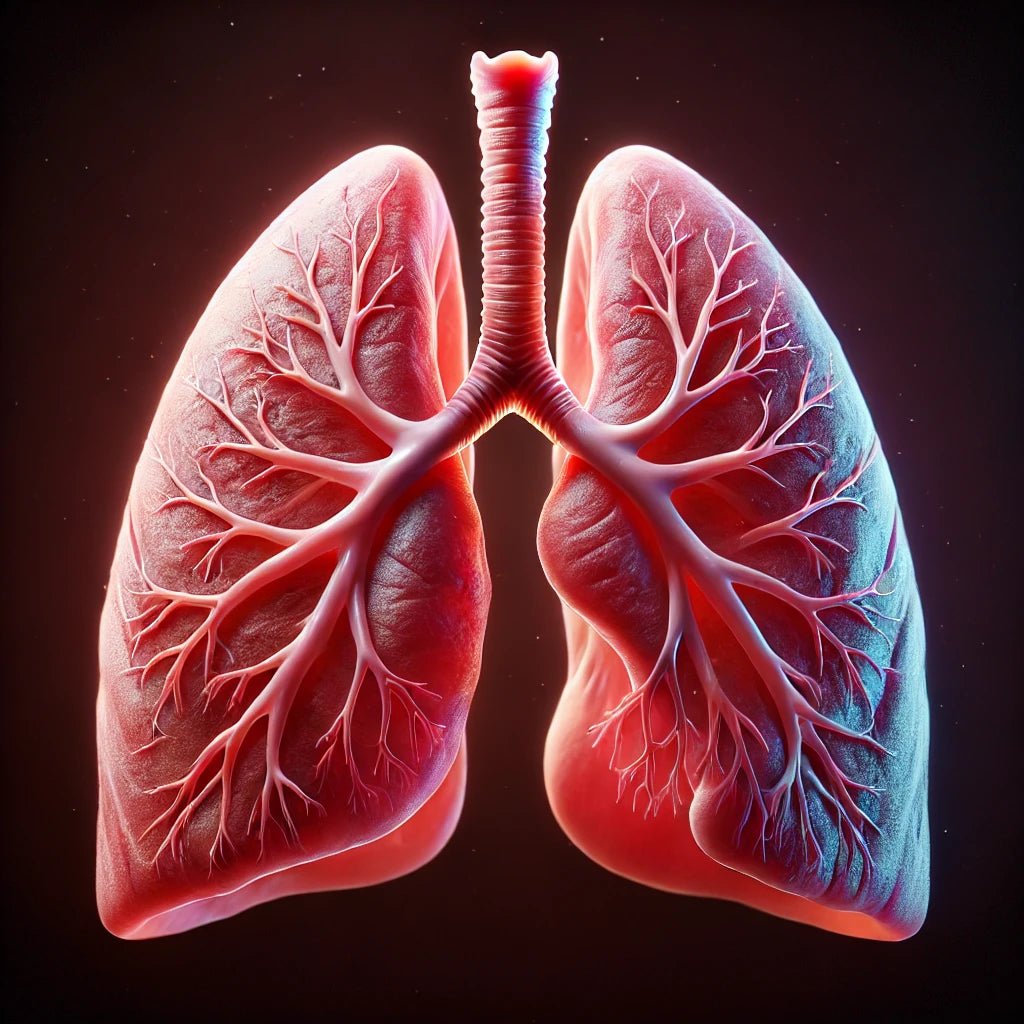

Your Lungs Need You

Interact with the image below for a fun, exaggerated representation of what quitting addictions and training your lungs can do!